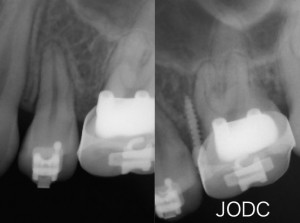

【3】TAD (矯正用インプラントアンカー)

矯正用インプラントアンカーと呼ばれる小さなネジのようなチタンスクリューを顎の骨に埋め込み、

アンカーを固定源とし大臼歯を遠心へ動かしていく治療です。インプラントアンカー1本埋入に要する時間は5〜10分程度で、矯正治療が終了したら口腔内から撤去します。通常のブラケットとワイヤーだけの矯正治療では、引っ張る力がワイヤーとつながった各々の歯にかかるので意図しない方向へ移動する事もあります。その点、矯正用インプラントアンカーを用いると歯を支点にする時と異なり、固定源が不動(移動する事がない)なので効率よく歯を動かす事が可能となります。

写真上が埋入時、写真下が3月後です。上顎犬歯を基準とし比較してみると全体的に遠心移動し上顎前突(出っ歯)も改善された事がよくわかります。上下顎の隙間が縮まりしっかりと咬めてますね。